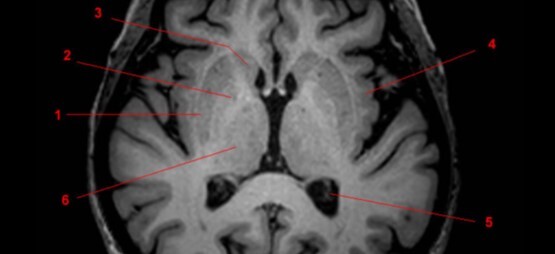

6

Q

Label 1-4

A

1. Lentiform nucleus

2. Caudate nucleus

3. Lateral ventricle

4. Cerebellum

How well did you know this?

7

1. Head of Caudate nucleus

2. Lateral ventricle

3. Thalamus